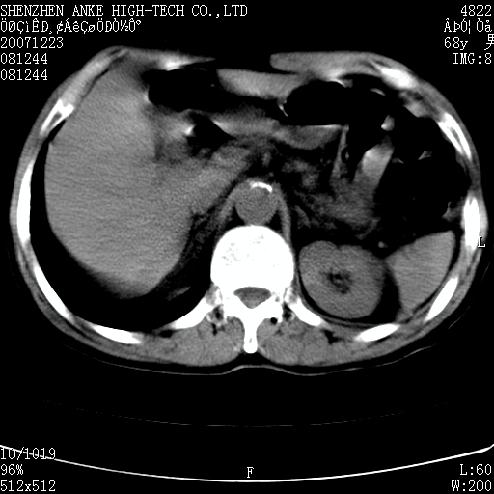

患者:男,63岁,2年前胆囊切除术后,现右上腹部剧烈疼痛近2天.

有无外伤史?右肾包膜下血肿可疑。

主要是问右肾有没有问题?患者无明显外伤史.

肠道准备不好,胃底后壁显示不清,右肾改变考虑为伪影。